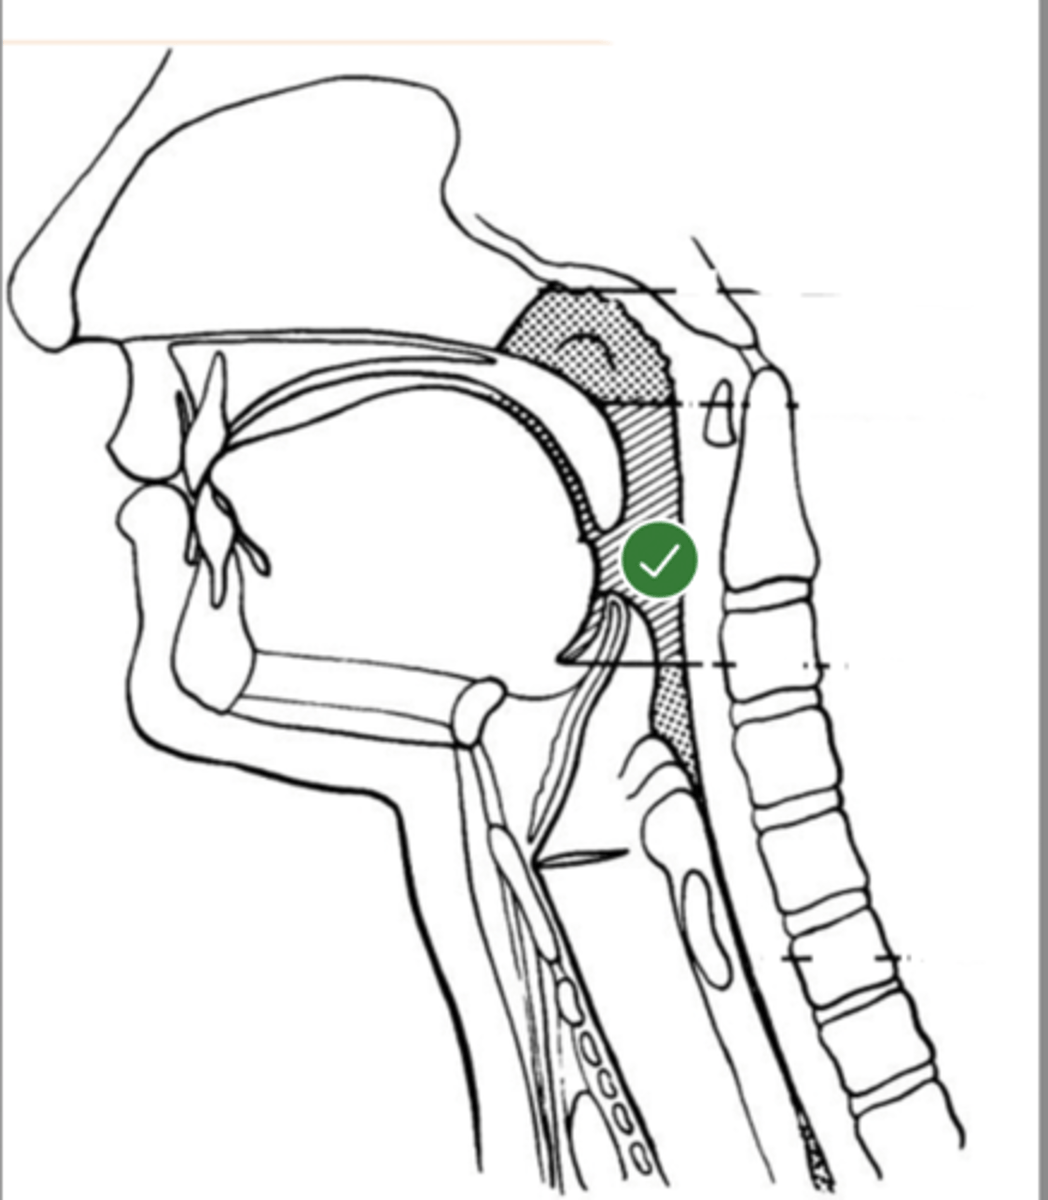

Label base of tongue (lateral view)

label anterior tongue (lateral view)

Label posterior/ back of tongue (lateral view)

Label Mandible (lateral view)

Label velum/ soft palate (lateral view)

Label hyoid bone (lateral view)

Label epiglottis (lateral view)

Label thyroid cartilage (lateral view)

Label posterior cricoid (lateral view)

Label trachea (lateral view)

Label upper esophageal sphincter (lateral view)

Label esophagus (lateral view)

Label posterior pharyngeal wall (lateral view)